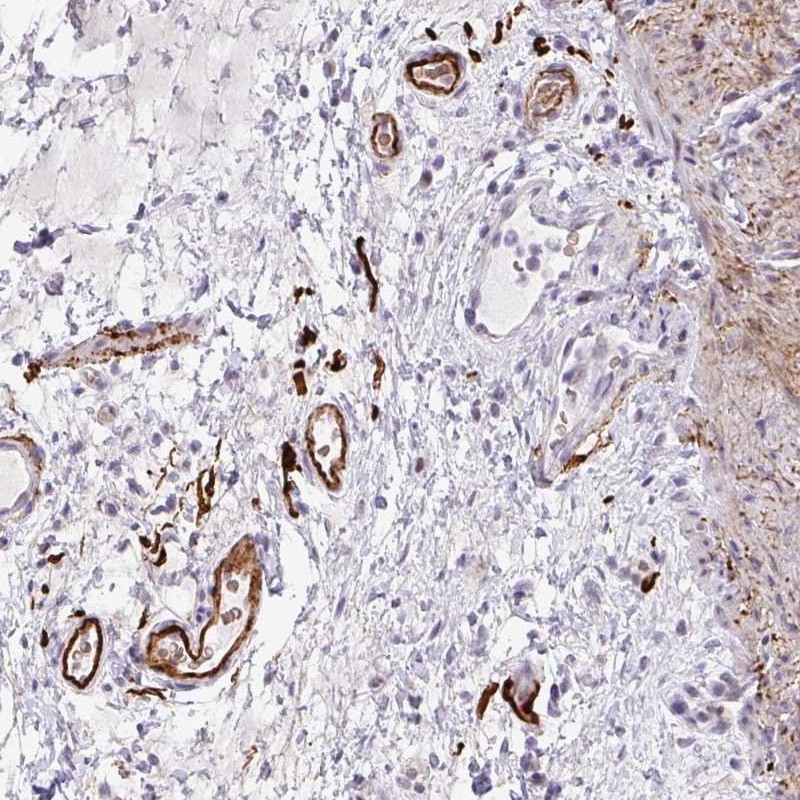

Immunohistochemical staining of human small intestine shows strong positivity in vessel wall.